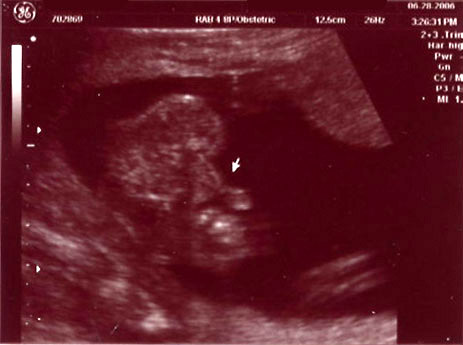

| May 2, 2006 - Twelve Week Ultrasound |

| Today was our

diagnostic ultrasound at the hospital. We got to see the baby dancing

all over the place. It was just so incredible. The technician

said that everything looked great and we were so happy to be able to see our

little bundle of joy. This was my second time seeing the baby on the

ultrasound, but this was Chris' first. He was so thrilled to see Baby

Palermo! ~Jen |